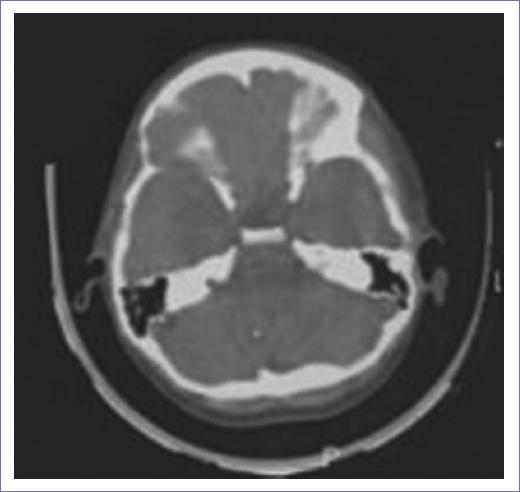

Hombre de 38 años sin antecedentes heredofamiliares y sociodemográficos de importancia, con antecedente de craneofaringioma resecado quirúrgicamente en 1992, con un total de 52 Gy en 25 sesiones de radioterapia en la región temporal. Comenzó en 2022, con parestesias en hemicara derecha, disminución de la agudeza visual en ojo izquierdo con cefalea recurrente y crisis focales sin pérdida del estado de alerta, motoras, con automatismos. Acude en agosto de 2023 con estudios de imagen (Fig. 1). Se halla con afección del segundo par, pupila izquierda 3 mm hiporreactivas, derecha 2 mm normorreactiva, fondo de ojo con atrofia de papila bilateral, presenta monocromatopsia, OD-20/40, OS- 20/200, la campimetría reporta hemianopsia heterónima bitemporal, dismetría ocular con divergencia ojo izquierdo, V1 y V2 derecho con disminución en la sensibilidad, con paresia del VII central derecho, Rinne negativo izquierdo, hipoacusia conductiva, desviación de úvula derecha, con reflejo nauseoso disminuido derecho, hipoestesia faríngea derecha.

Figura 1 Último estudio tras la radiación, con el cual se da de alta al paciente en 2008, sin lesión residual o alguna otra.